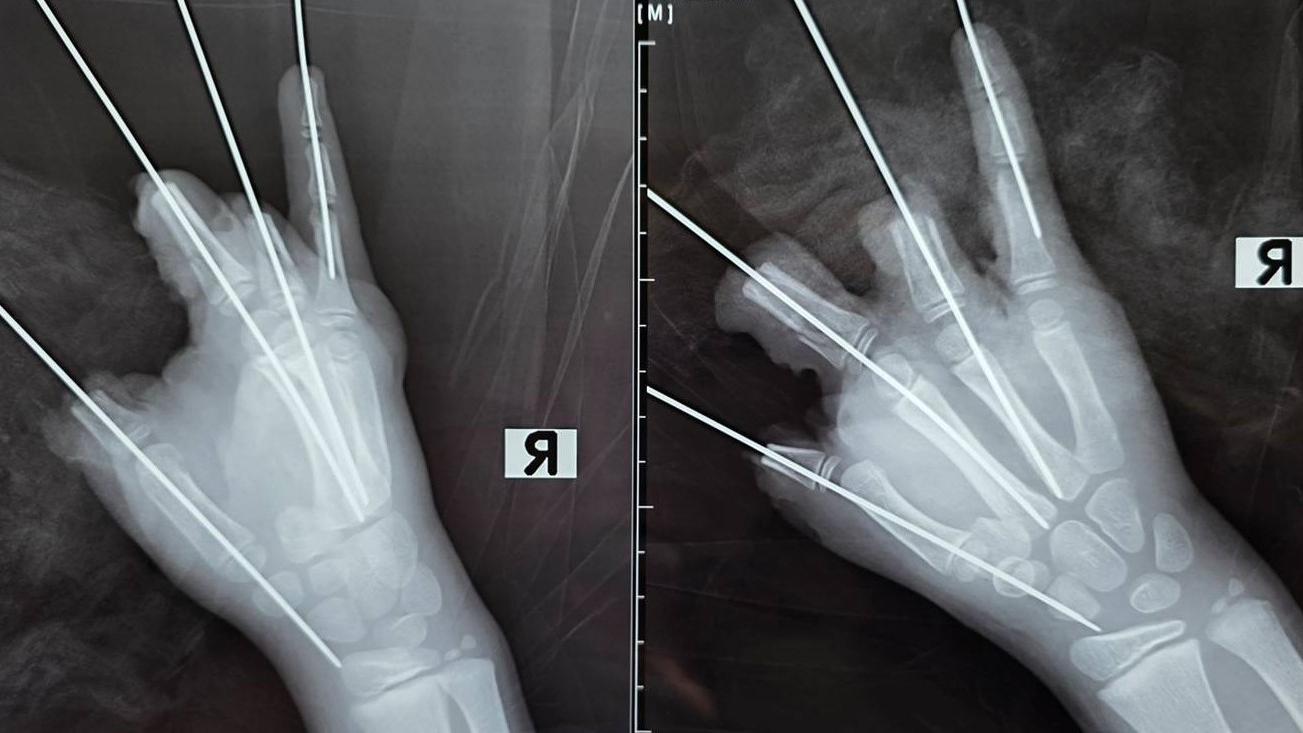

Сообщается, что взрыв привёл к травматической ампутации четырёх пальцев и к значительному повреждению мизинца. У пострадавшего диагностировали открытый перелом и вывих пястной кости. Также врачи констатировали размозжение и дефекты мягких тканей.

Врачи доставили мальчика в Педиатрический университет в 21:40, пострадавшего тут же поместили в операционную. Специалисты удалили свободно лежащие фрагменты костей, соединили отломки фаланг среднего и безымянного пальцев, а также удалили нежизнеспособные ткани и сформировали культи большого, среднего и безымянного пальцев.